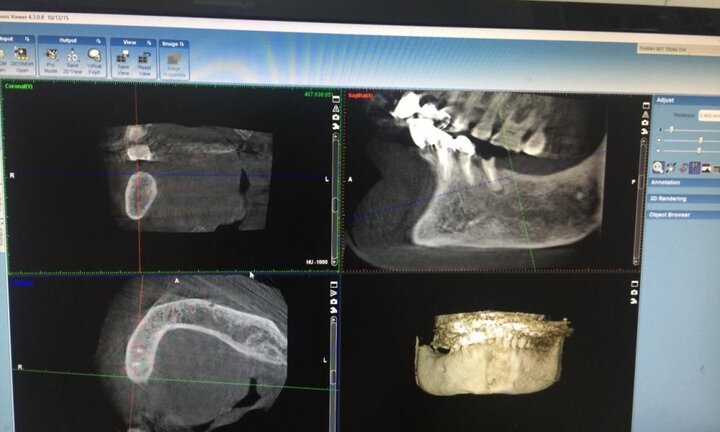

GS. TS. Trịnh Đình Hải, Giám đốc Bệnh viện Răng hàm mặt Trung ương cho biết, lần đầu tiên, các bác sĩ ngành răng hàm mặt Việt Nam đã thực hiện ca phẫu thuật, cấy ghép răng cho một cụ bà trên nền bệnh cao huyết áp.